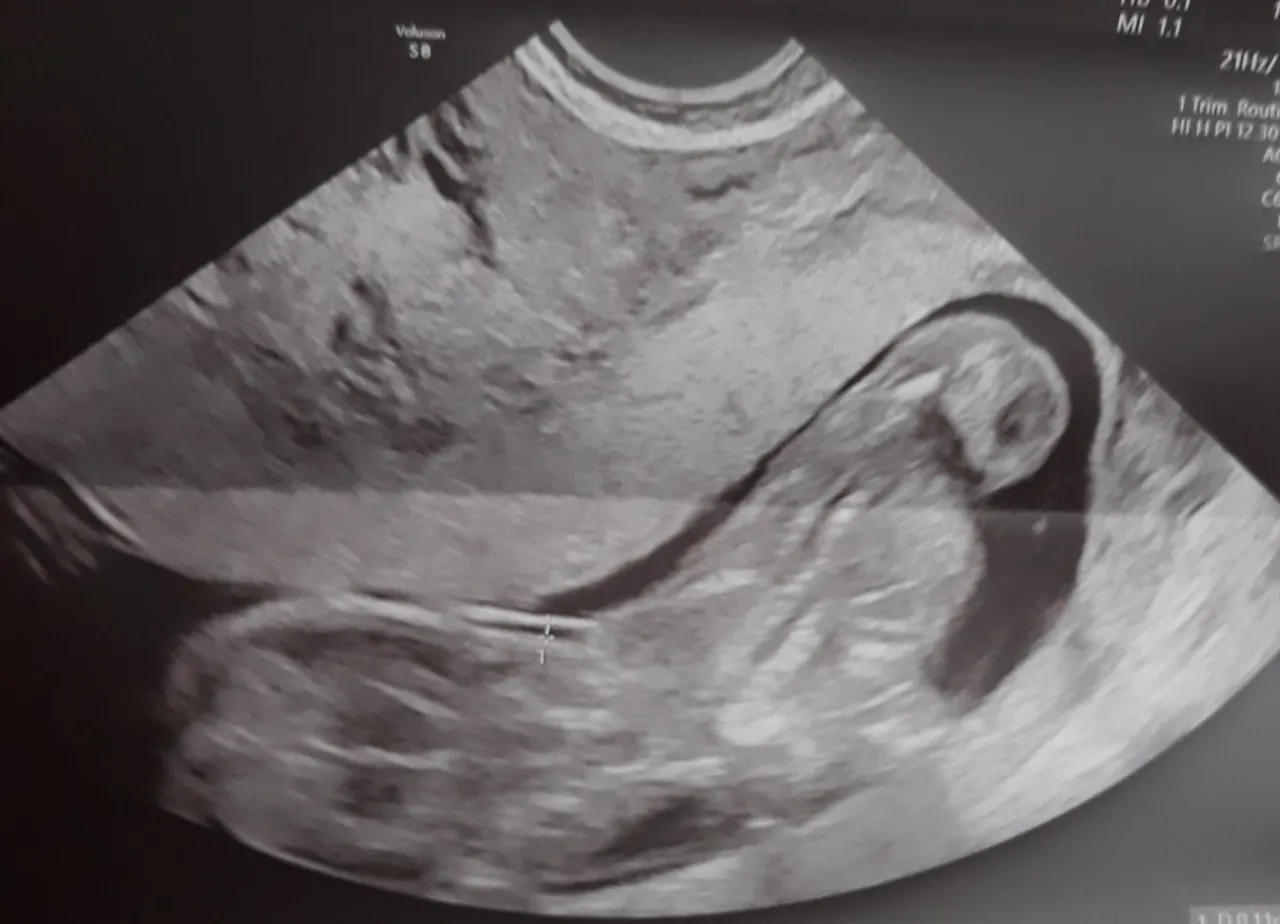

USG genetyczne I trymestru: ostatni moment na kluczowe badanie

13. tydzień ciąży to ostatni dzwonek na wykonanie niezwykle ważnego USG genetycznego I trymestru, które przeprowadza się między 11. a 14. tygodniem. To badanie ma kluczowe znaczenie, ponieważ pozwala ocenić ryzyko wystąpienia wad genetycznych u dziecka, takich jak zespół Downa. Nie przegap tego terminu to cenne źródło informacji o zdrowiu Twojego maluszka.

Jak interpretować wynik przezierności karkowej (NT)?

Jednym z kluczowych elementów USG genetycznego jest pomiar przezierności karkowej (NT), czyli grubości płynu pod skórą na karku płodu. Wynik tego pomiaru, w połączeniu z innymi parametrami (np. obecnością kości nosowej) oraz badaniami biochemicznymi z krwi matki (test PAPP-A), pozwala oszacować ryzyko wystąpienia niektórych wad chromosomowych. Pamiętaj, że jest to badanie przesiewowe, a nie diagnostyczne, i jego interpretacja zawsze powinna odbywać się w porozumieniu z lekarzem.